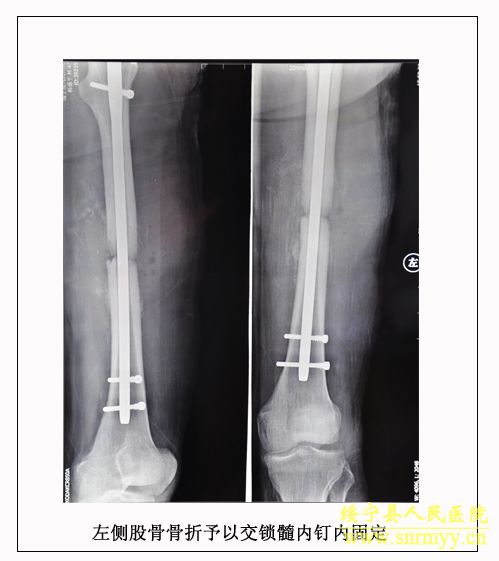

经检查:当时病人体温36.5℃、脉搏105次/分钟、呼吸25次/分钟、血压152/98mmhg,呈昏迷状,头面部、右手、左下肢均不同程度受伤,双侧瞳孔不等大,光反射消失;同时右手臂和左大腿均有骨折。GCS评分:仅4分,根据评分标准(轻度颅脑损伤为12—15分、中度为8—12分、重度为5—8分、极重度为3—5分)该病人属于极重度颅脑损伤。CT检查结果为脑干挫裂伤、双侧额叶、左颞叶、右顶叶脑挫裂伤、左侧颞部硬膜外、下血肿,左顶硬膜下血肿,蛛网膜下腔出血,脑室内积血,左侧额部下积液,左眼框内侧壁,枕骨骨折。X光片显示右桡骨粉碎性骨折,左股骨干骨折。诊断为:1、极重度颅脑损伤:(1)脑干挫裂伤。(2)双侧额叶、左颞叶、右顶叶脑挫裂伤。(3)右颞部硬膜外血肿。(4)外伤性蛛网膜下腔出血。(5)枕骨骨折。(6)头皮多处挫裂伤。2、右桡骨粉碎性骨折。3、左股骨干骨折。临床上如此严重的脑损伤死亡率极高,再加上合并多处骨折创伤,病人危在旦夕。

经再次检查,病人的身体状况明显好转,但意识模糊。9月28日,病人意识逐渐清楚。为方便护理,让病人早日康复,由沈建辉副院长亲自主刀,刘兴淼医师为助手,为病人实施了左股骨开放复位和交锁髓钉内固定术。10月21日,病人生活基本能自理,近日即可出院。 (2010.10.26)